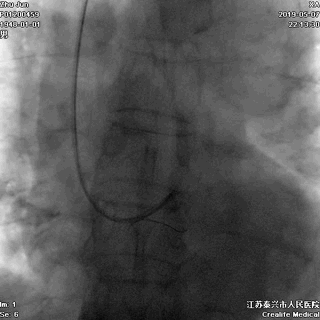

右冠状动脉无严重病变

游离一根导丝至升主动脉,防止导管深插

轻轻冒烟,证实指引导管到位

轻轻冒烟,大致了解前降支的情况